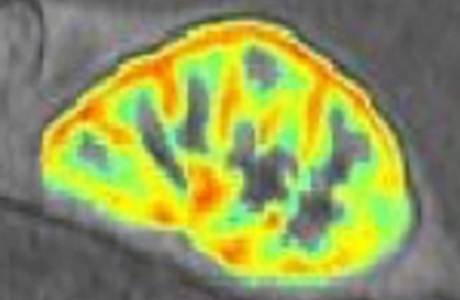

Individualisierte Diagnostik der chronischen Nierenerkrankung Transnationales Forschungsprojekt RESPECT im Rahmen des ERA-Netzes zur Personalisierten Medizin PerMed gefördert

MRT-Messung und farbcodierte Darstellung der Nierenperfusion UMMEin Verbund von Forschungsgruppen aus sechs europäischen Ländern hat sich im mehrstufigen Begutachtungsverfahren des Joint Transnational Call 2020 des ERA-Netzes PerMed*, welches transnationale Projekte zum Thema personalisierte Medizin fördert, mit seinem Projekt RESPECT durchgesetzt. RESPECT** hat zum Ziel, die Behandlung...